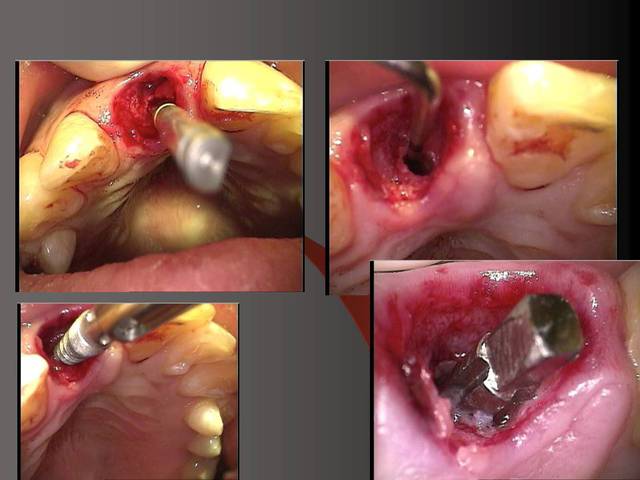

Photos d'un cas d'extraction implantation immédiate, stabilité primaire (de mémoire) assez élevée.. 60/70 N ..démontage du gingiva clips et du shuttle, pilier serré 40N, couronne procera

Sur la photo 5 on voit que je prépare surtout le titane de l´implant, le titane ne donne pas beaucoup du chaud quand il est préparé avec l´eau (pas comme aluminium par exemple).

En dessous il y a des photos, dans une on voit (troisième) qu il n y a pas de resorption de l´os après 14 ans, ce que l´on voit c´est l´os très fin condensé sur l´implant.

Le premier photo c´est une erreur parce que le périoste est blessé et les foret "trop" grands.